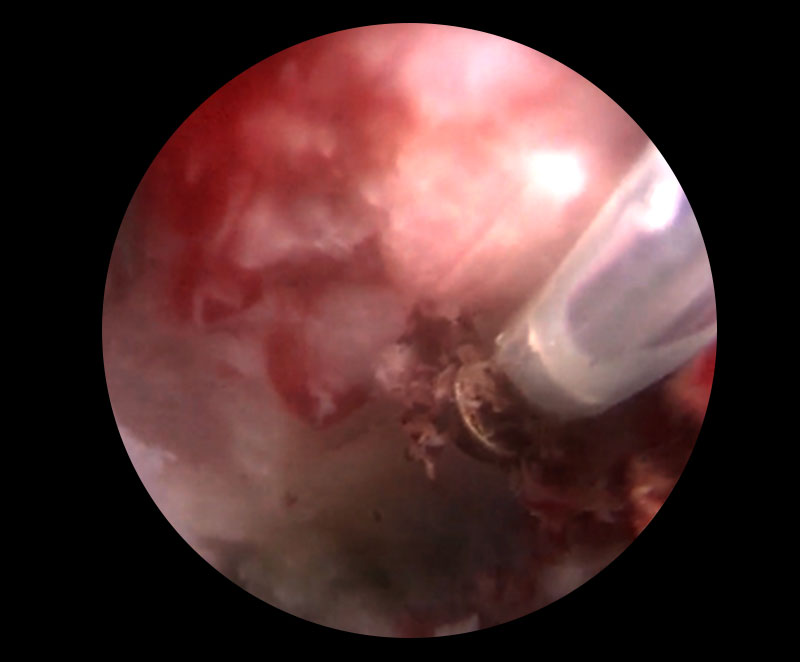

全内視鏡下脊椎手術は、局所麻酔下に8mmのひとつのポータルを経椎間孔的に作成し、内視鏡を挿入します。他の整形外科分野の内視鏡下手術と同様に、生理食塩水で灌流しながら、必要に応じて3mmのハイスピードドリルで骨を削り、鉗子でヘルニアを切除します。途中、出血があれば、ラジオ波バイポーラで止血を行います。他の脊椎用手術器具と異なり経皮的に行う手術なので、器具がどれも長いのが特徴です。

内視鏡を使って低侵襲に病変部へアプローチ

ヘルニアを切除

ヘルニアを摘出